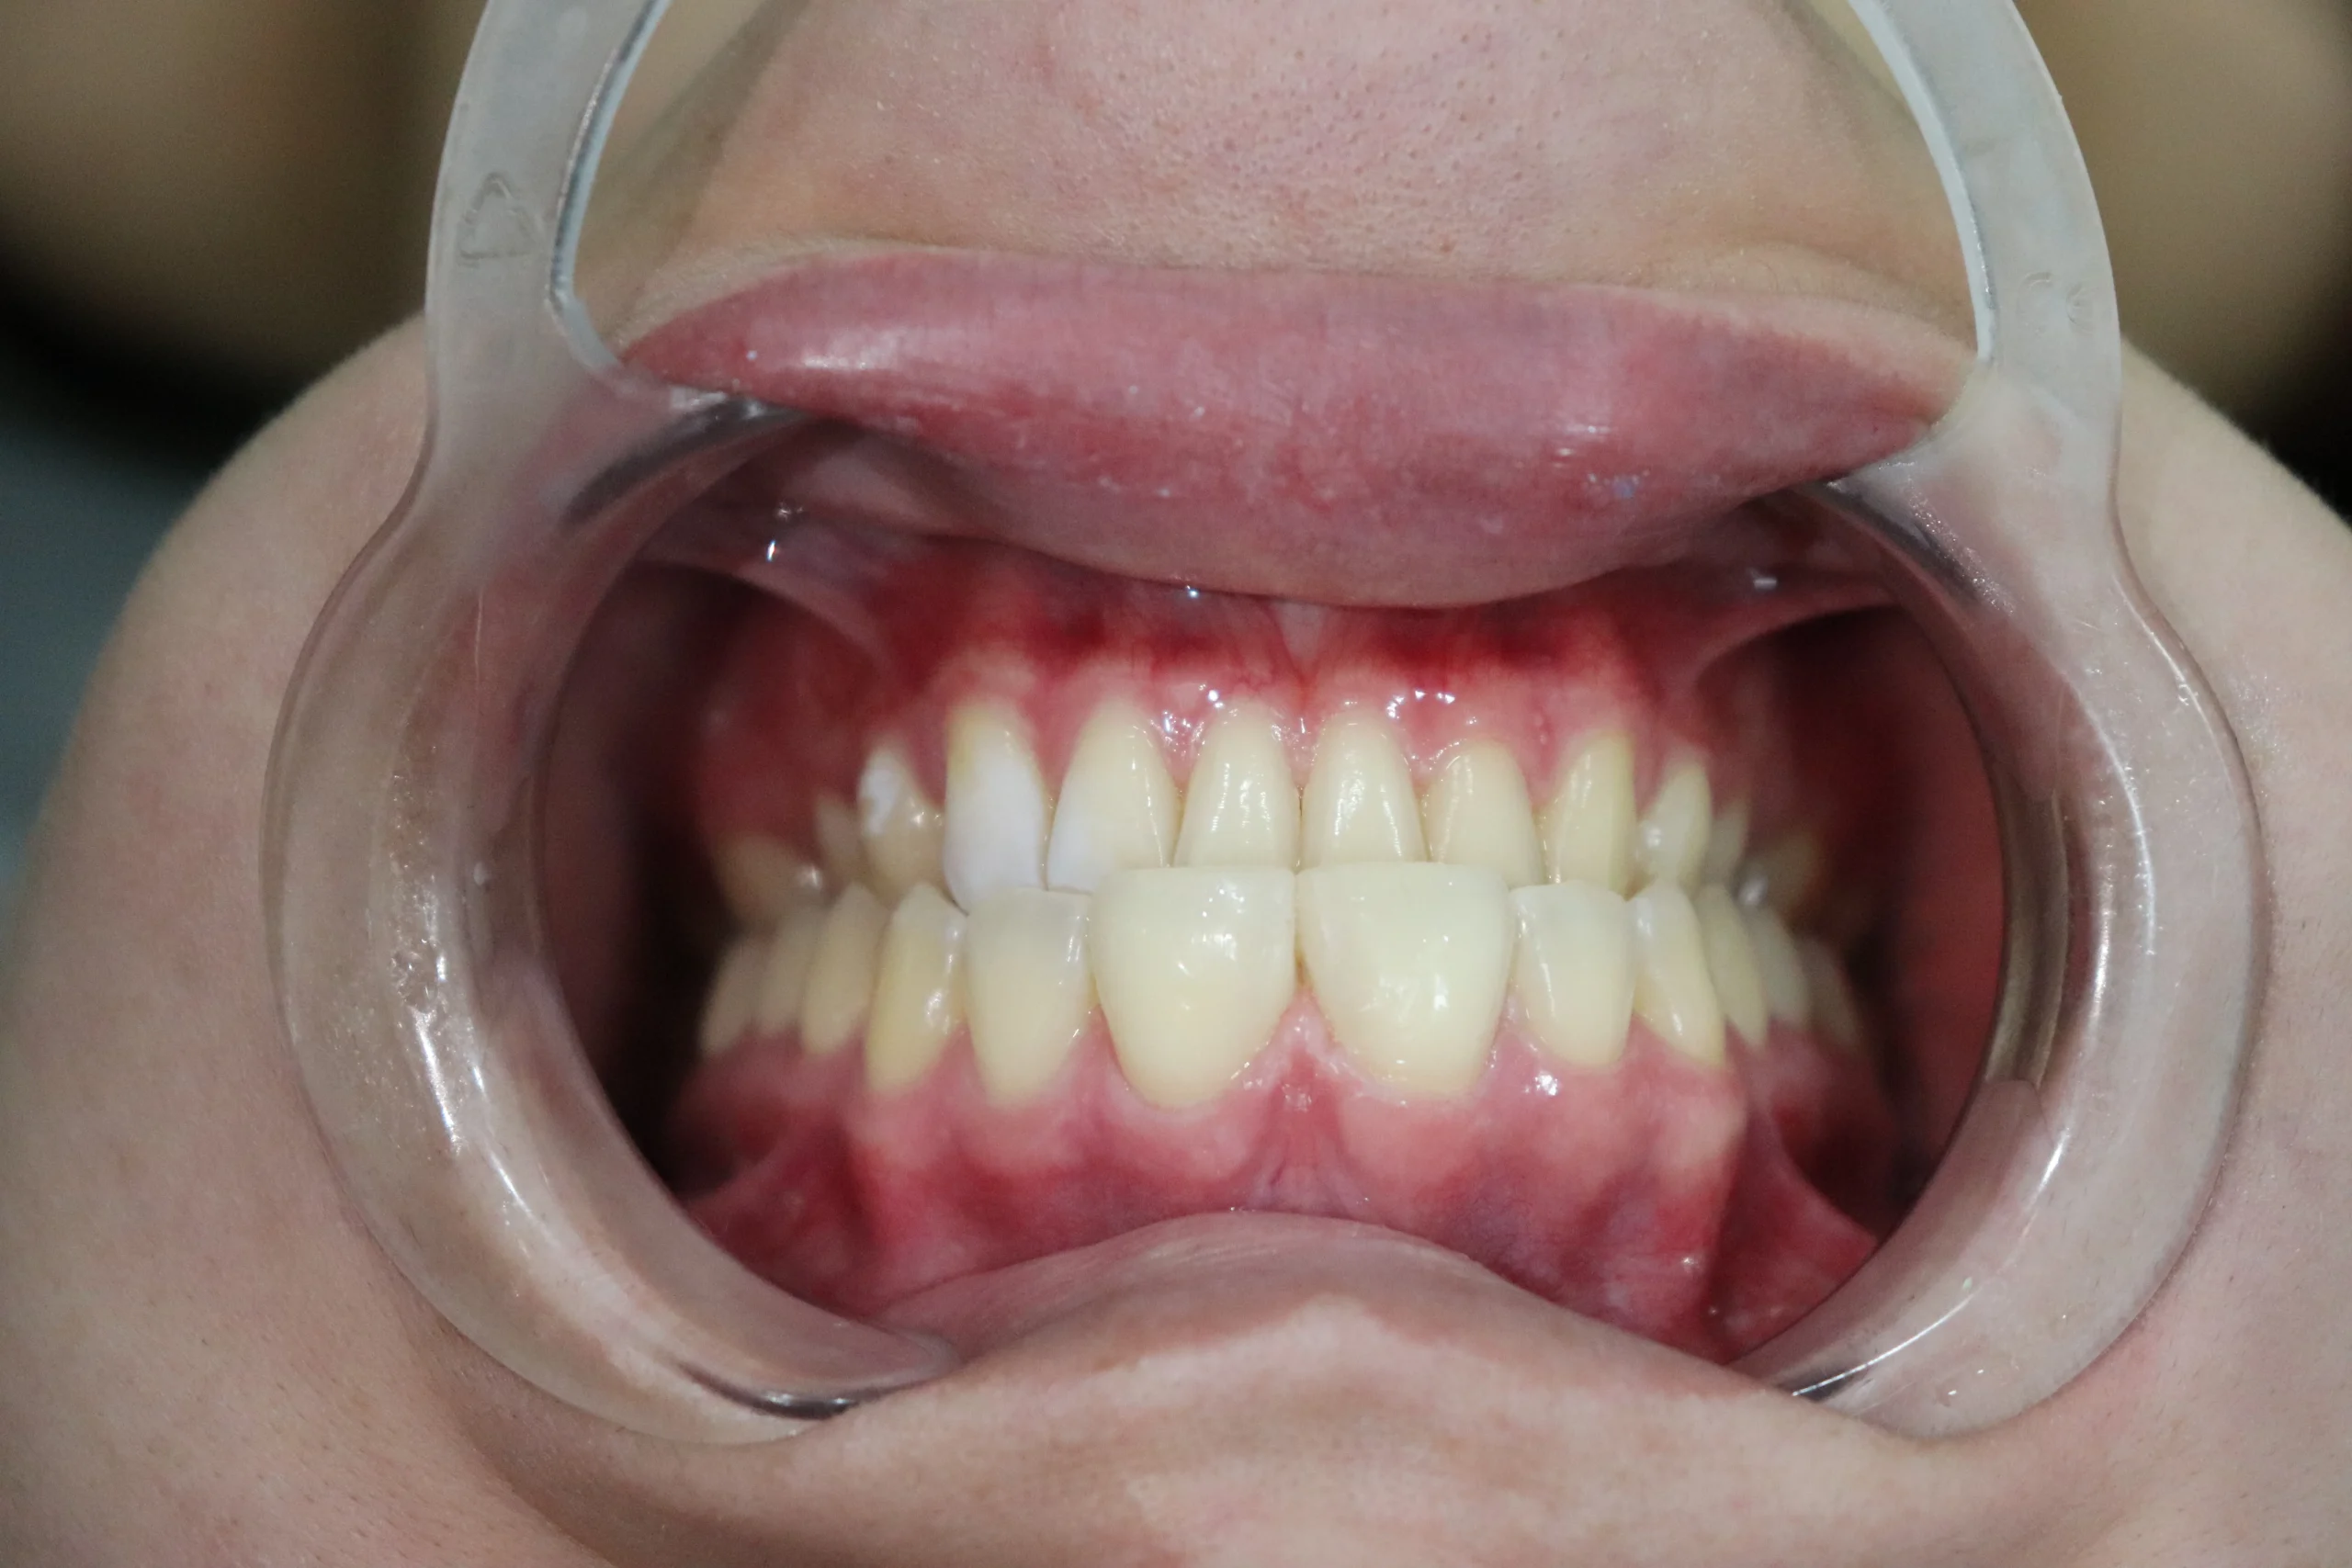

Esta paciente acudió a consulta manifestando inseguridad al sonreír, causada por un espacio visible entre sus dientes anteriores. Luego de una evaluación estética y funcional, conversamos sobre las distintas opciones de tratamiento disponibles.

Finalmente, se decidió realizar un cierre de diastema utilizando resina compuesta, una técnica conservadora y altamente estética que permite corregir el espacio sin desgastar el esmalte dental.

Antes